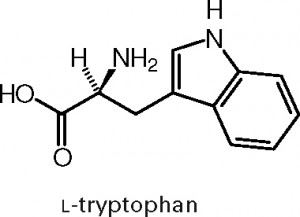

yine bir başka aminoasit olan ve mutlulukta rol oynayan triptofanı ele alalım: triptofan aminoasiti yapısında indol halkası bulundurur. bu halka vücudunuz tarafından sentez edilemez ve dışarıdan almak zorundasınızdır. zaten bu tip aromatik aminoasitlerin hepsi esansiyel aminoasit gruplarıdır.

şu gördüğünüz triptofan aminoasiti. halkalardan üstteki olan indol halkasıdır ve bu halkaya dikkat ediniz.